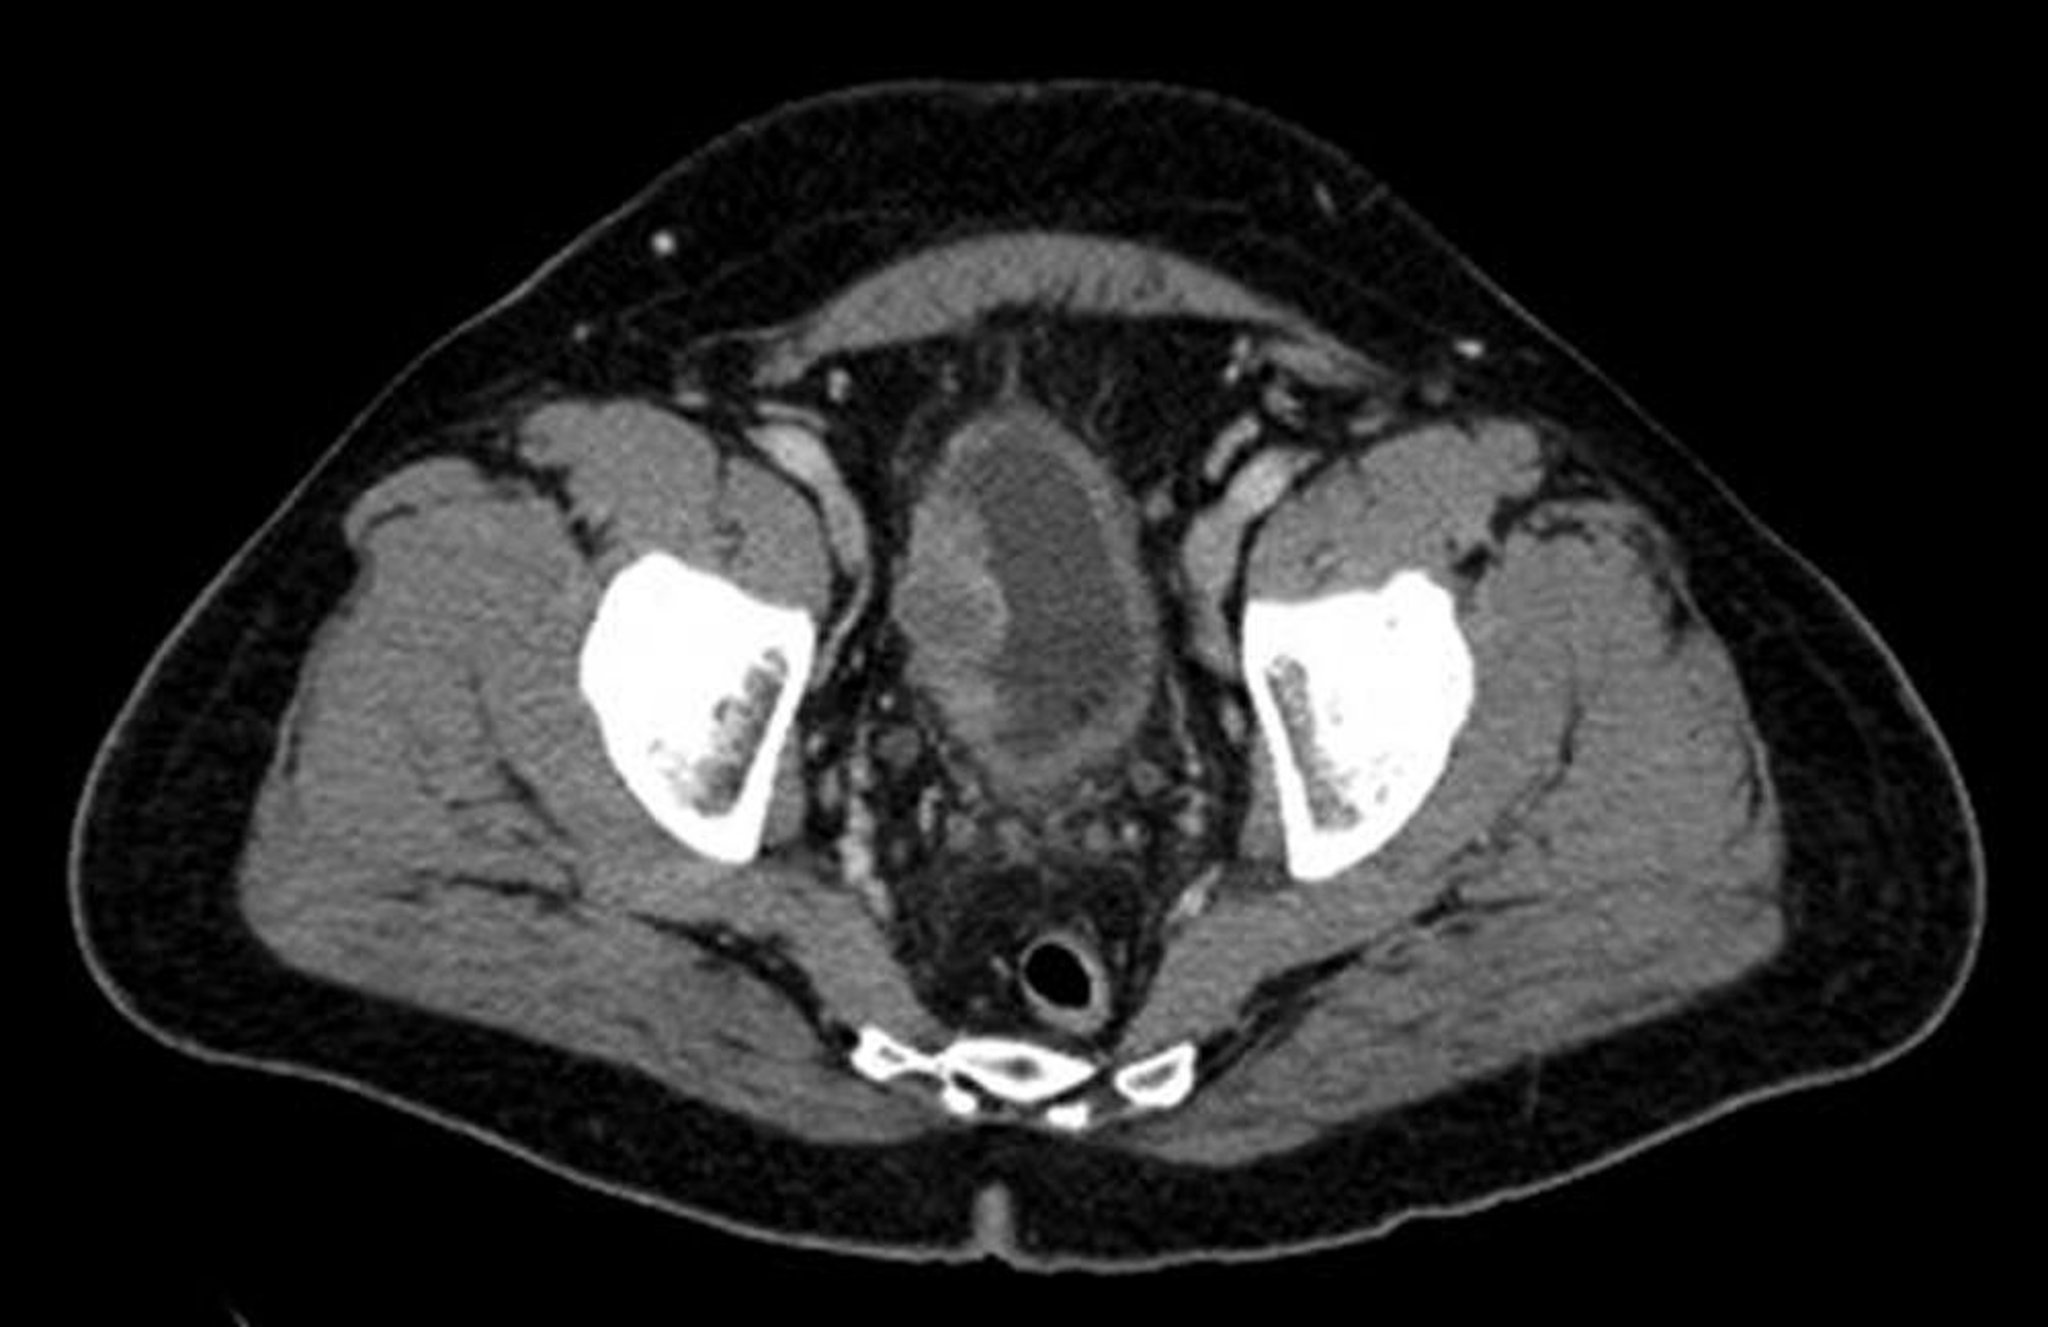

For nonmuscle-invasive bladder cancer (carcinoma in situ, Ta, T1) tumors, which comprise 70 to 80% of bladder cancers, cystoscopy with biopsy (with simultaneous complete resection) is sufficient for staging. However, if biopsy shows the tumor is more invasive than a superficial or flat tumor, then repeat resection should be considered within 4 to 8 weeks, taking care to include muscle tissue. If a tumor is found to invade the detrusor muscle ( stage T2), blood tests, abdominal and pelvic CT, and chest x-ray are done to determine tumor extent and evaluate for metastases. MRI can be considered for local staging. Patients with invasive tumors undergo bimanual examination (rectal examination in men, rectovaginal examination in women) while under anesthesia for cystoscopy and biopsy. The standard TNM (tumor, node, metastasis) staging system is used (see table AJCC/TNM Staging of Bladder Cancer and table TNM Definitions for Bladder Cancer).